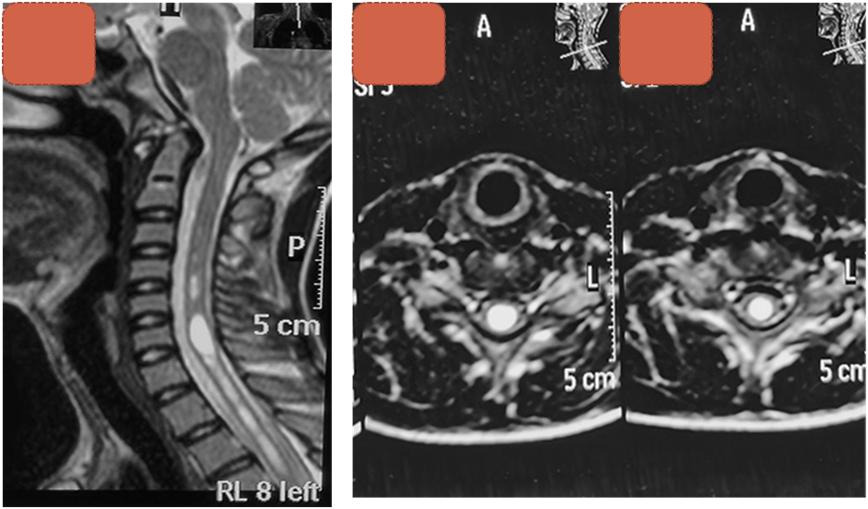

详细检查发现,这位少年患有罕见的严重脊柱侧弯伴脊髓空洞症,核磁共振显示,在其颈髓和胸髓内均有明显的脊髓空洞。脊柱侧弯本身会影响脊髓功能,严重侧弯又会造成脊髓空洞的加重。

术前核磁可见脊髓空洞